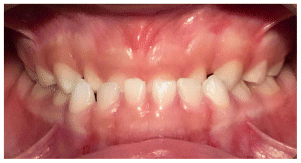

Case 2

The patient was a growing female child who presented during early mixed dentition with an anterior crossbite associated with a deep overbite and a marked sagittal discrepancy (Figures 12–19). The initial clinical examination revealed a negative overjet, complete anterior deep bite, and a functional Class III occlusal pattern. Extraoral assessment showed a flattened facial profile, while cephalometric analysis confirmed a skeletal imbalance characterized by increased SNA and SNB values, an ANB of 0°, negative Withs appraisal, and significant dentoalveolar compensations, including proclination of both upper and lower incisors (Table 3). The vertical pattern was predominantly hypodivergent, suggesting a high risk of unfavorable mandibular growth progression if left untreated. Given the patient’s young age and growth potential, an early interceptive treatment was planned to use the AMCOP® TC appliance, with the aim of correcting the anterior crossbite, improving neuromuscular balance, and guiding sagittal and vertical development during growth. The appliance was worn nightly and for additional daytime hours, according to patient compliance.

After 18 months of treatment, a clear clinical improvement was observed. Intraoral examination demonstrated complete correction of the anterior crossbite, with establishment of a positive overjet and normalization of the anterior occlusal relationship. The deep bite was reduced, allowing more functional anterior guidance. Occlusal relationships improved toward a stable dental Class I, and the need for excessive dentoalveolar compensation was reduced. Cephalometric reassessment showed an overall improvement in sagittal relationships and incisor inclinations, with a trend toward normalization of the previously altered parameters. These findings indicate that early functional therapy with the AMCOP® TC appliance was effective in intercepting the developing Class III malocclusion, improving occlusal function, and potentially reducing the severity of future skeletal discrepancies (Table 4).